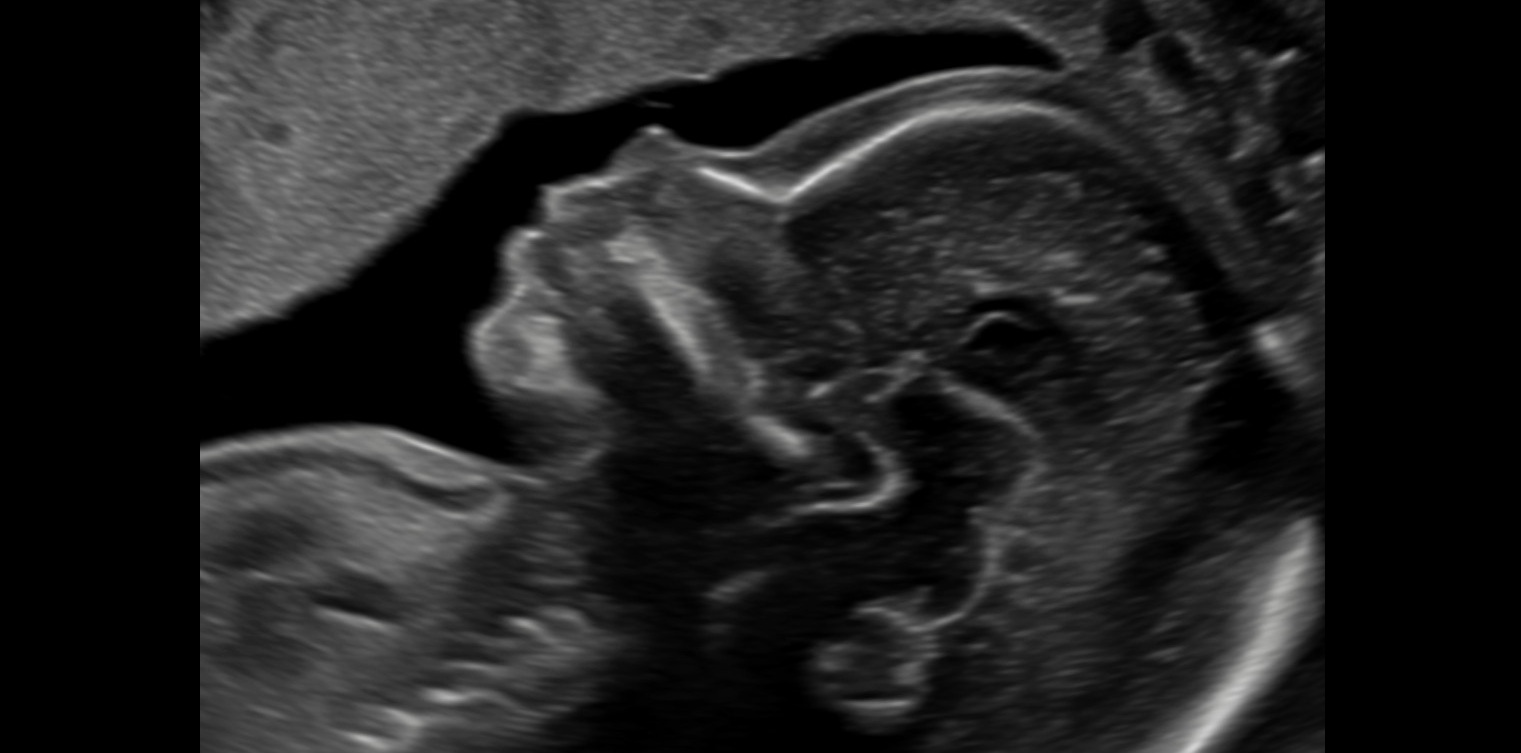

„Feindiagnostik“: 20-24 SSW

Wir schauen Ihr Kind im Ultraschall detailliert von Kopf bis Fuß an. Mit Fortschreiten der Schwangerschaft liegt der Fokus hier besonders auf der Entwicklung von Herz und Kopf Ihres Kindes. So können wir Besonderheiten frühzeitig erkennen, die Schwangerschaft optimal begleiten und die Geburt bestmöglich vorbereiten. In manchen Fällen ist eine Behandlung bereits während der Schwangerschaft möglich.

Je nach Fragestellung kann diese Untersuchung auch zu einem deutlich früheren oder späteren Zeitounkt sinnvoll sein.